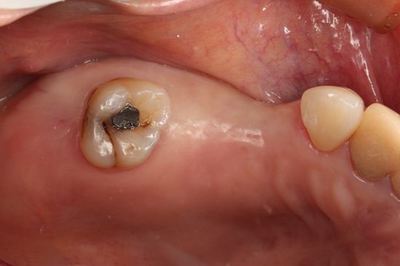

左上ミラー像です。クビレが存在しています。

術前との比較です。アマルガムも今後除去します。